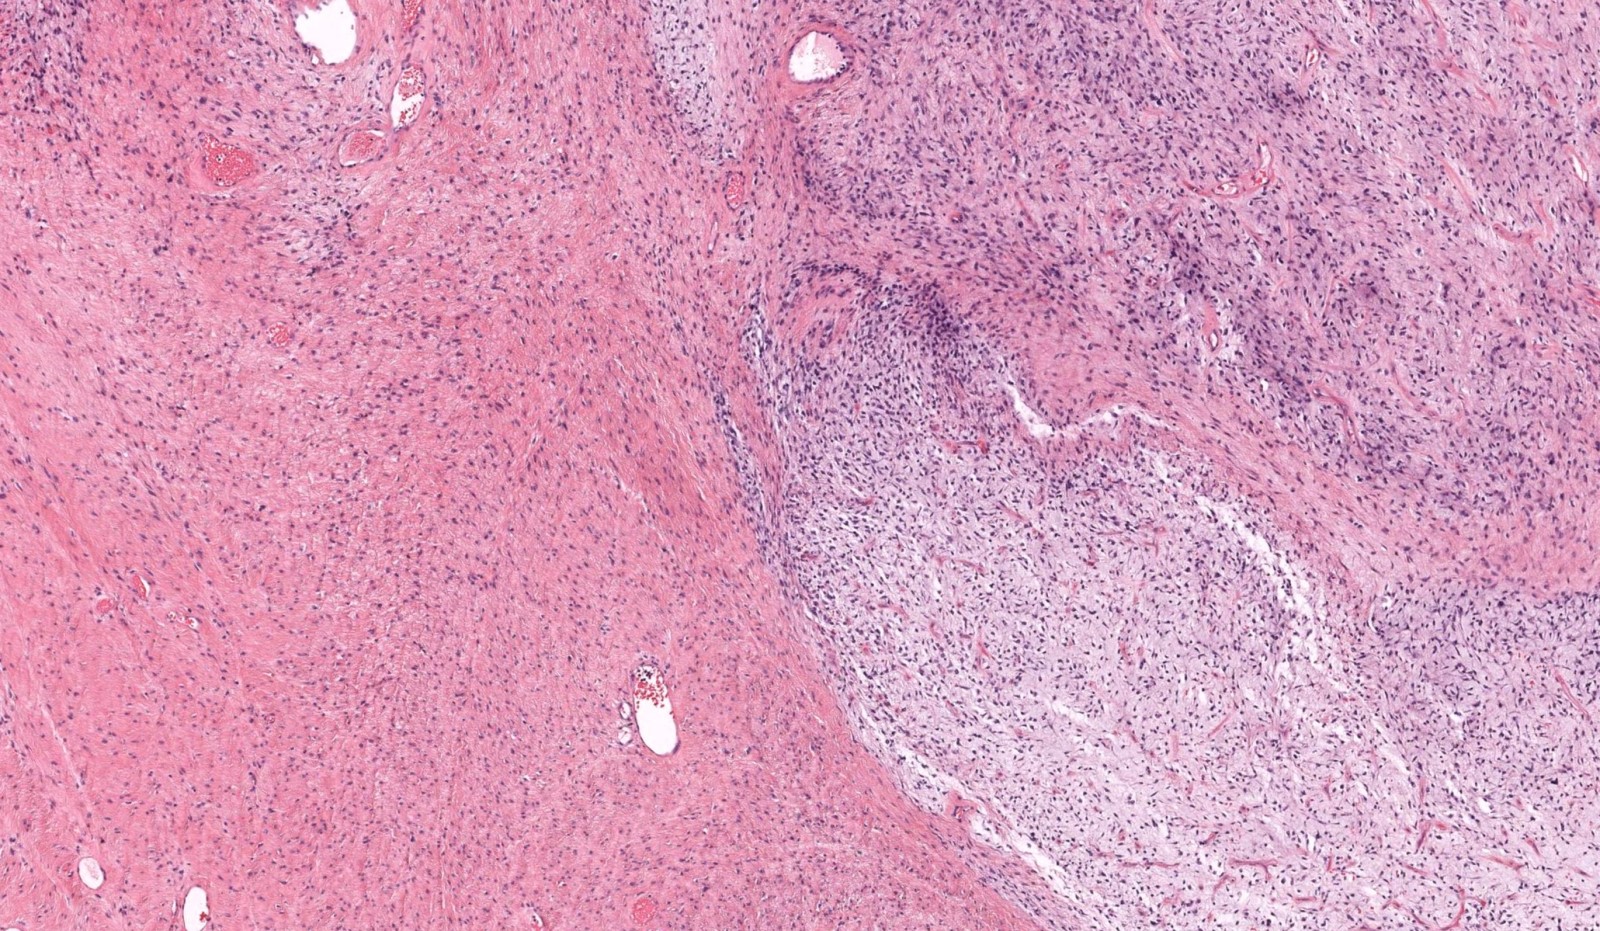

Microscopic (histologic) description

- Low to moderately cellular, bland fusiform or spindled cells with focal to diffuse whirling in heavily collagenized stroma with abrupt transition to myxoid areas

- 45% have epithelioid areas

- 40% contain poorly formed but large collagen rosettes

- Often infiltrates adjacent skeletal muscle

- Occasionally has areas of increased cellularity, atypia, necrosis or mitotic activity characteristic of intermediate to high grade sarcoma

- Recurrences may show increased cellularity and mitotic activity